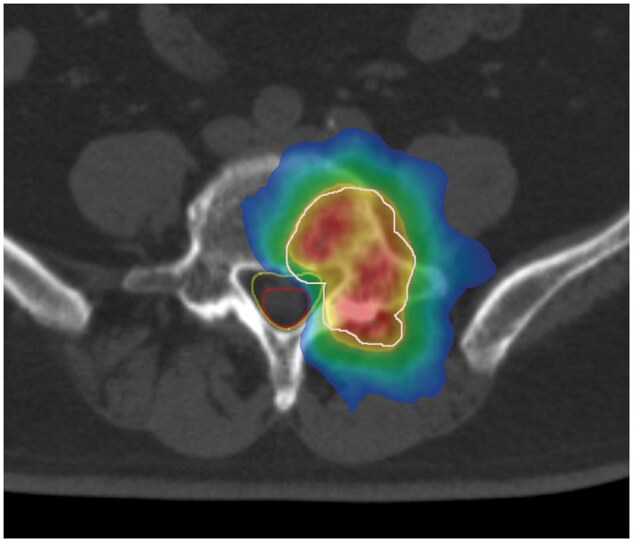

Setting the echo time to zero allows for the acquisition of bone images that were otherwise difficult to obtain with conventional MRI and clear visualization of CT-like MR images. This technique is mainly useful for detecting compression fractures; however, studies examining bone tumours have been lacking. Furthermore, no reports to date have investigated the usefulness of MRI for evaluating images before and after radiotherapy (RT) for bone tumours. Therefore, plain CT and MRI (T1/T2-weighted image and CT-like MRI) were performed under the same conditions before and after radiation therapy (RT) and examined the obtained images. An 86-year-old man received RT (30 Gy/3 fraction) for painful lumbar metastasis from prostate cancer. At 2 months after RT, no changes in T2-weighted images and plain CT scans were noted, but CT-like MRI showed an increase in the signal inside the bone metastasis. Examining how the images change over time is imperative given the difficulty of predicting the duration of the pain relief effects of RT for bone metastases. Therefore, the current case report explored whether combining various modalities, such as CT and MRI, could predict prognosis. We highlight the importance of investigating whether signal changes are correlated with pain symptoms and whether MRI can be a predictor.

Abstract Image